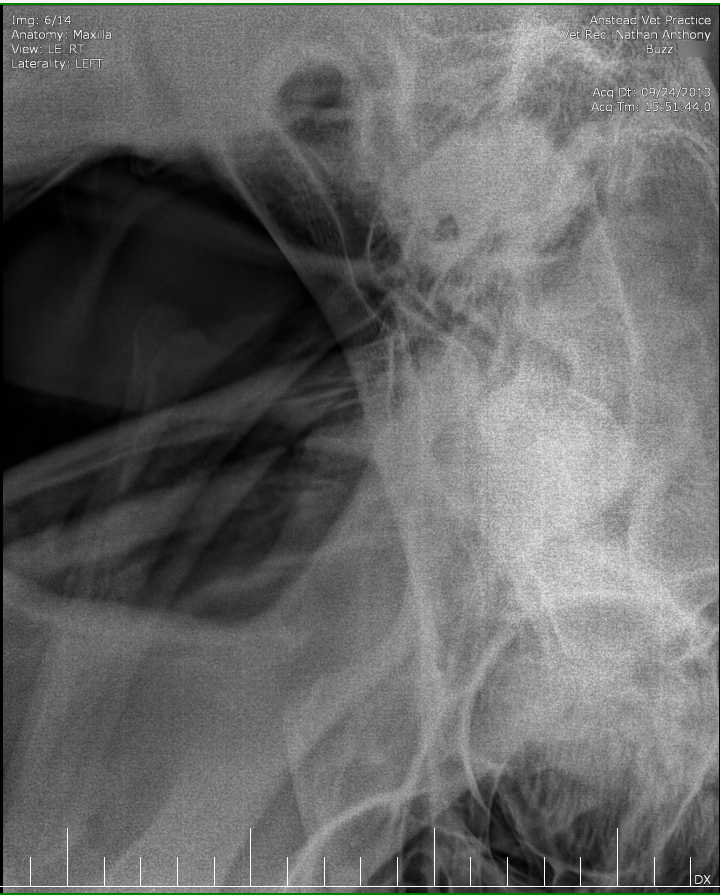

Posted on Sunday, May 8, 2016 - 6:24 pm: Thank you for the welcome!I did contact the lab to see if they still had the samples but they will only speak to the vets who submitted the samples. I've asked my vet to ask on my behalf but haven't yet heard back yet. The horse has been scoped and I was told that it all looked normal. The stylohoid bone and guttural pouches normal. The inflammation is mostly around the nostrils as per the pic but there are a couple of small spots further up inside the nose. He's also had his skull xrayed which I'm told also looked normal. I've included the pics at the bottom. I've included a list of other things here that have been tested to see if they influence the shaking or inflammation for the better or worse: - experimental course of Equity - Flixotide via inhaler - high dose of prednisolone - did work! - low dose of prednisolone - did not work - teeth checked by two different vet dentists - fly masks & nose nets - relocated him to several different places in the city incase it's an environmental allergen - all sorts of feed supplements - removed all hard feed, just feeding hay - stabled him 24/7 and fed him Haygain steamed hay incase it was something in the paddock - light/dark makes no difference to the shaking - it's not seasonal, happens year round I've also had bloodwork done and it showed a low red blood cell count. The blood was taken two weeks after the biopsies. My vet didn't think the low count was attributed to the blood loss from the biopsies so he suggested parasites but a worm count came back clean. I also had a test to see if there was blood in the manure, but nothing was found. There was no plan made to address the low RBC. Results are attached in a text file to maintain the spacing.

Xray images: